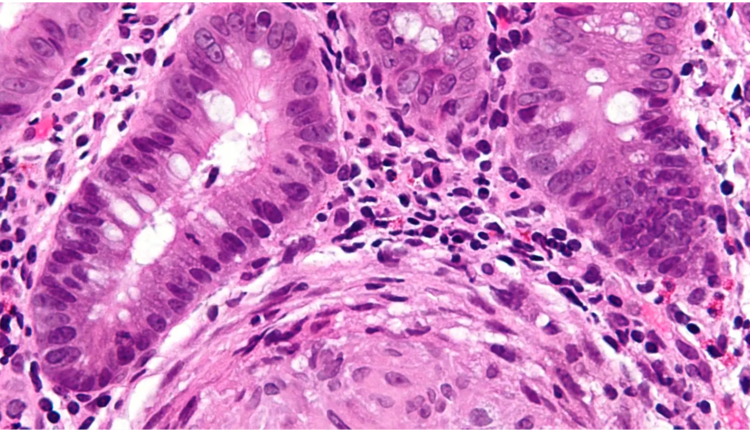

Bilim insanları, Crohn benzeri semptomlar geliştirmek için yapılan farelerin yanı sıra Crohn teşhisi konan insanlardan biyopsi alınan bağırsak dokusu örneklerini incelediler. Her iki grupta da yaralı veya iltihaplı doku çevresinde bol miktarda D. hansenii buldular, ancak sağlıklı insanlardan alınan örneklerde veya Crohn hastalarının iltihaplanmamış dokusunda D. hansenii bulunmadı.

Örneğin, bir grup Crohn hastasından alınan yedi örneğin hepsinde mantar buldular, ancak karşılaştırma olarak kullanılan 10 sağlıklı kontrolden sadece birinde. Ayrıca, bu mayanın farelerde bağırsak yaralarının yavaş iyileşmesiyle doğrudan bağlantılı olduğuna dair kanıtlar buldular. Ve bir Crohn hastasından veya hastalıklı farelerden mantar örnekleri alıp yeni bir sağlıklı fare grubuna verdiklerinde, farelerin bağırsak yaralarını iyileştirme yeteneği daha da kötüleşti. Bu etki daha sonra farelere antifungal (mantar iyileştirici) tedavi uygulandığında tersine döndü.